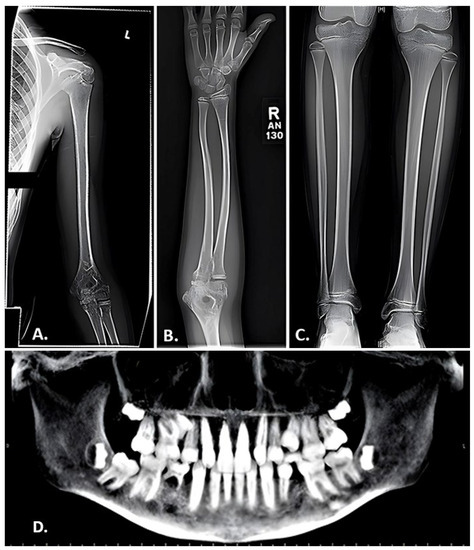

- Littman, J.; Phornphutkul, C.; Saade, C.; Katarincic, J.; Aaron, R. Osteoporosis, Fractures, and Blindness Due to a Missense Mutation in the LRP5 Receptor. Orthop. Res. Rev. 2023, 15, 39–45. [Google Scholar] [CrossRef] [PubMed]